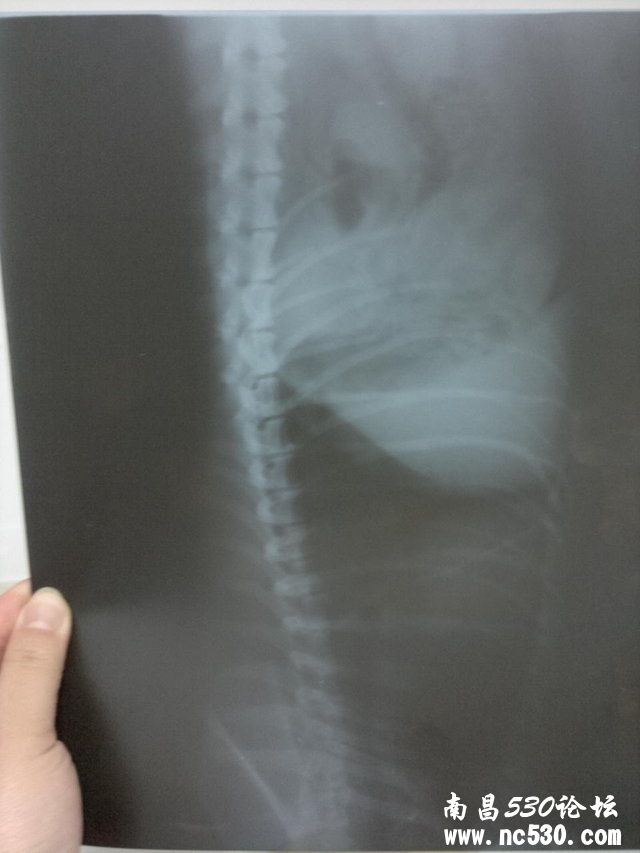

2011-12-24 01:18    动物种类:狗 动物品种:京巴串

动物年龄:11

性别:母

免疫情况:二个月时打过五联疫苗以后没有再打过

是否绝育或去势:否,下过六窝仔,七岁以后就没再让下过.

精神状态:不如以前精神

食欲如何:不想吃饭

排便如何:正常,一天最少二回,形状颜色都很好 症状:大概有一个月了,没精神总爱趴着,有时呼吸间身体有轻微拌动,睡觉有时会喘几下,溜弯时不爱走近几天不爱吃饭. 12月18日在家附近的宠物诊所诊断说心肌肥大,第二天发现外阴流脓水诊断子宫蓄脓,后有医生说开放型的叫子宫内膜炎,现在打消炎针.

麻烦张医院给看看下边的片子12月18日拍的,因为我们这边没有正规的宠物医院还劳烦张医生给确诊下

这个是心脏病吗是哪种呢需要怎样治疗,可以吃药吗,吃哪种药比较好.还有心脏病的话可以输液吗?